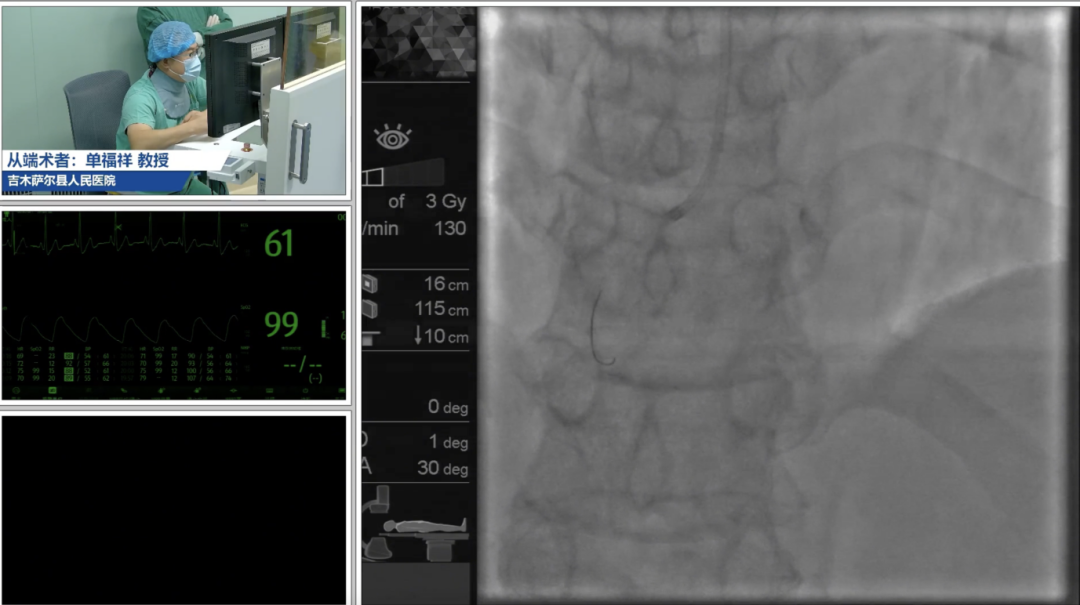

本次培训是《5G技术操控R-One™机器人用于经皮冠状动脉介入治疗手术平台应用》援疆项目的主要内容之一,既有高年资专家的理论授课,又有疑难病例的深度研讨和设备的模拟操作。新疆维吾尔自治区人民医院杨毅宁教授、吉木萨尔县人民医院解玉涛教授以致辞开篇,介绍5G远程冠脉介入机器人手术平台的应用现状。随后,新疆维吾尔自治区人民医院杨毅宁教授、王钊教授,吉木萨尔县人民医院单福祥教授,新疆维吾尔自治区人民医院余小林教授和知脉(上海)机器人林蕾博士分别从前沿进展、临床应用、临床策略和实操技巧、项目进展、以及研发和技术保障等方面介绍了该技术的前沿进展和现状,通过手术演示,术中同步讲解,术后案例讨论,学员结合自身临床经验提出疑问,专家团队针对临床策略、应用经验等内容逐一解答。培训过程中,学员结合讲解进行了模拟操作,进一步了解该技术的操作细节。